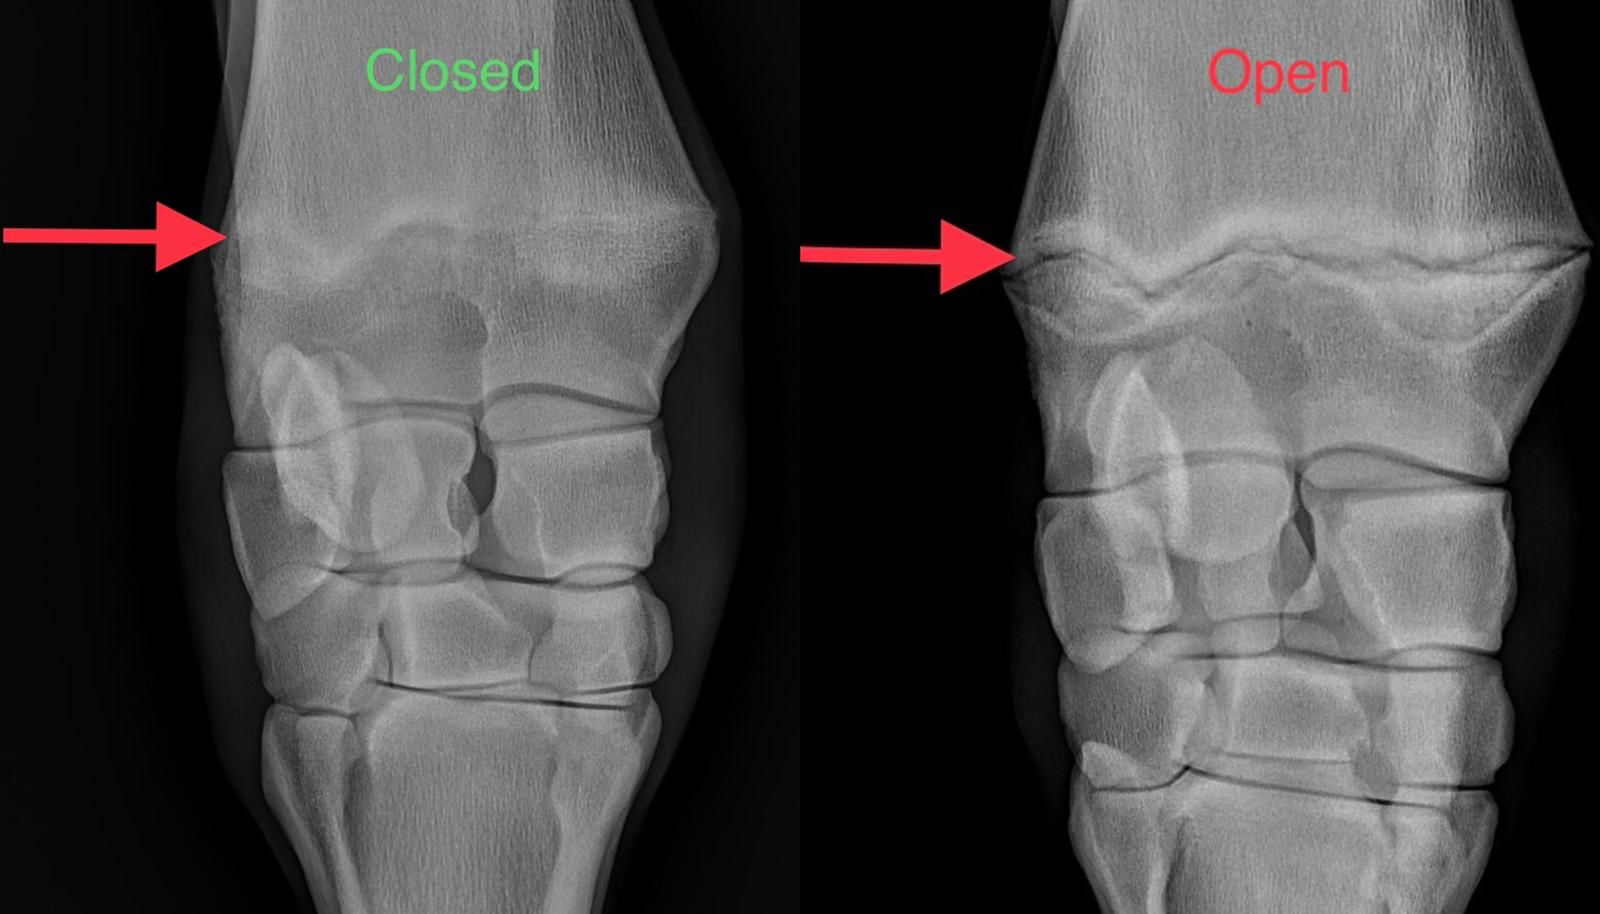

Heres my radiology it is over or not ?

Im 6’4 ( 192 ) and 16 yo in one month